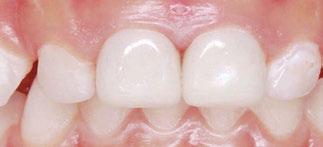

Several clinical solutions exist for primary anterior teeth with multisurface decay. Full coronal restoration of carious primary incisors may be indicated when caries is present on multiple surfaces, pulpal therapy is indicated, caries may be minor, but oral hygiene is very poor, or in a child with severe early childhood caries or a high caries risk diagnosis.1 Depending on the clinical scenario, a minimally invasive approach with the utilization of a high viscosity glass ionomer cement (HVGIC), with or without the combination of silver diamine fluoride (SDF) in a strip crown form, may pause the caries progression and provide an adequate clinical solution. Resin composite strip crowns have shown 80% retention rates and adequate parental satisfaction,1-4 although composite resin strip crowns have shown lower retention rates in teeth with decay involving three or more surfaces and particularly in children with a high caries risk4-6 (Figure 1). This could be from the continued high caries risk behaviors of the patient, as composite resin strip crowns in this population have shown to have increased inflamed marginal gingiva and gingival bleeding, increased plaque retention along the restoration, and loss of some restorative material.5,6

Alternatively, a resin-faced stainless steel crown provides a full coverage restoration with excellent retention.7 These crowns can serve as a full-coverage restoration with or without the resin facing, but the loss of resin facing can be a major esthetic concern for parents.7 Preformed pediatric zirconia crowns address many of the undesirable clinical outcomes of other restorative materials. Their biocompatibility, demonstration of excellent marginal gingival health, low plaque retention, high parental esthetic acceptance, and high survival probabilities make them an excellent clinical choice in the patient with severe early childhood caries.1,4,5,8-13

With parental interest increasing in esthetic treatment options for complex anterior caries, preformed pediatric zirconia crowns are becoming the treatment of choice for patients with a high caries risk or a severe early childhood caries diagnosis.14

2: NuSmile® Anterior Zirconia crowns at 2-year follow up. Note the high amount of plaque accumulations along the untreated cuspid and existing stainless-steel crowns

Figure 1: Occlusal films at recall visit in high caries risk patients showing loss of material and recurrent decay in composite resin strip crowns Figure

around these clinical sites. His anterior zirconia crowns showed healthy gingival margins with little-to-no plaque accumulations. This positive clinical finding is from the highly polished nature and biocompatibility of pediatric zirconia crowns. These restoration features limit plaque accumulations on the restoration and along the marginal gingiva, providing a localized positive aspect directly related to the choice of restorative material (Figure 2).